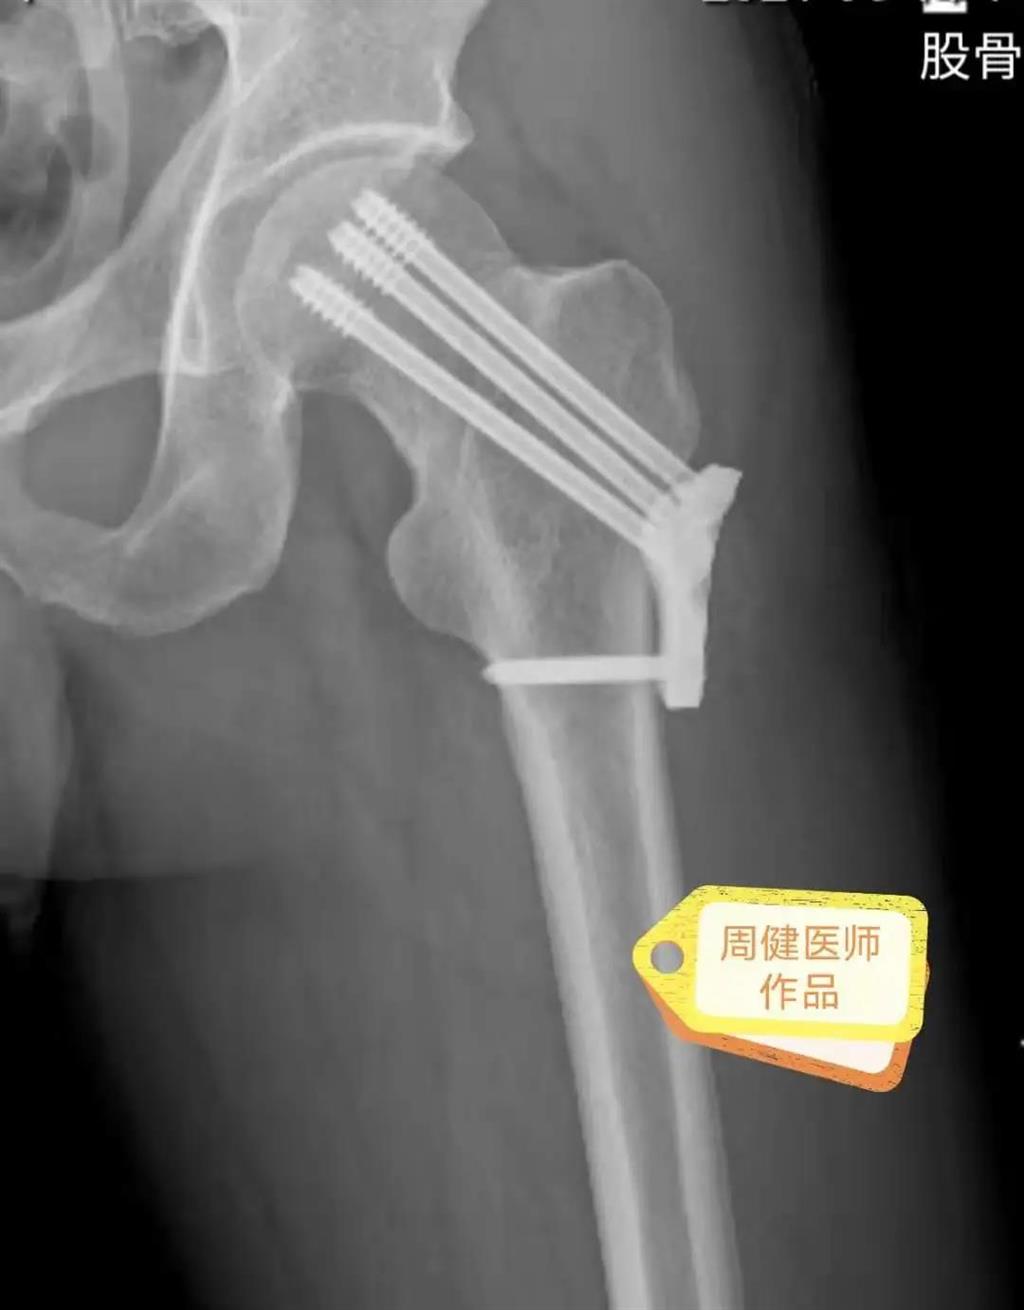

6月30日的“關(guān)節(jié)置換術(shù)”,患者是一位上了年紀的老人,苦于病痛折磨多年的他四處“求醫(yī)問藥”,最后在多位專家醫(yī)師及病友地力薦下選擇了和平國際醫(yī)院,在醫(yī)師團隊“偷天換日”般的手術(shù)后,老人成功告別了苦纏多年的病痛。

周健說,這場“關(guān)節(jié)置換術(shù)”對于他們團隊而言其實算是比較普通的手術(shù),因為做過很多同類的手術(shù),成功案例繁多,因此在手術(shù)操作上有較多地實操經(jīng)驗。“不過話雖如此,作為醫(yī)生我們對于每一場手術(shù)都會全力以赴,這是為醫(yī)者的職責也是義務(wù)。”